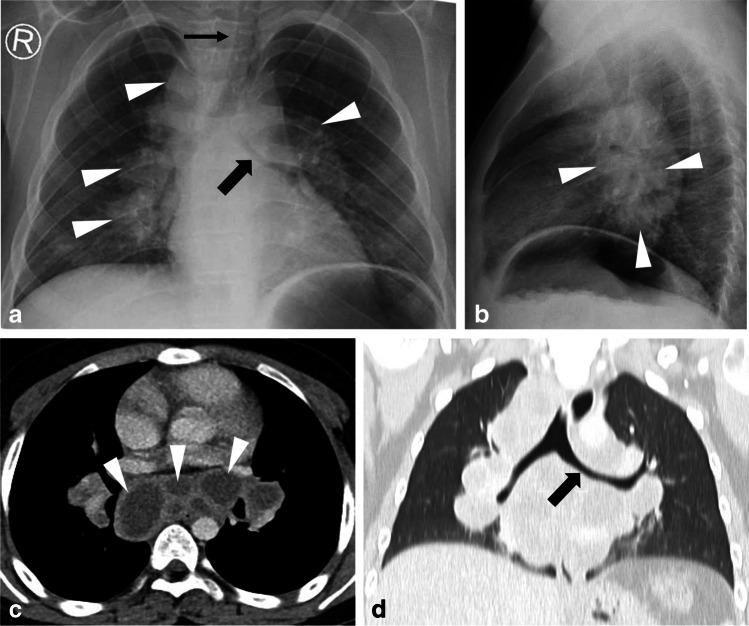

Tuberculosis (TB) remains a global health problem and is the second leading cause of death from a single infectious agent, behind the novel coronavirus disease of 2019. Children are amongst the most vulnerable groups affected by TB, and imaging manifestations are different in children when compared to adults. TB primarily involves the lungs and mediastinal lymph nodes. Clinical history, physical examination, laboratory examinations and various medical imaging tools are combined to establish the diagnosis. Even though chest radiography is the accepted initial radiological imaging modality for the evaluation of children with TB, this paper, the first of two parts, aims to discuss the advantages and limitations of the various medical imaging modalities and to provide recommendations on which is most appropriate for the initial diagnosis and assessment of possible complications of pulmonary TB in children. Practical, evidence-based imaging algorithms are also presented.